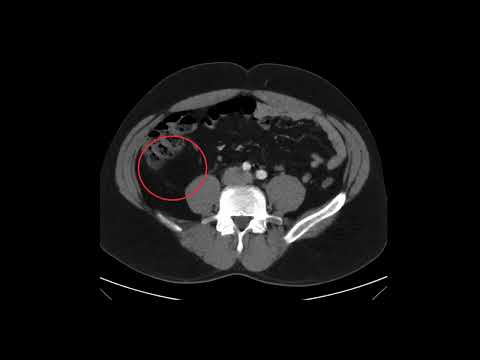

Massive Traumatic Retroperitoneal Hematoma, CT Annotated

Massive Traumatic Retroperitoneal Hematoma, CT Unannotated